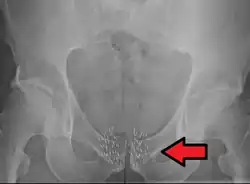

Arrow points to brachytherapy beads used to treat prostate cancer.

Prostate cancer

Brachytherapy to treat prostate cancer can be given either as permanent LDR seed implantation or as temporary HDR brachytherapy.[1]: Ch. 20 [33][34]

Permanent seed implantation is suitable for patients with a localised tumour and good prognosis[33][35][36][37] and has been shown to be a highly effective treatment to prevent the cancer from returning.[35][38] The survival rate is similar to that found with EBRT or surgery (radical prostatectomy), but with fewer side effects such as impotence and incontinence.[39] The procedure can be completed quickly and patients are usually able to go home on the same day of treatment and return to normal activities after one to two days.[6] Permanent seed implantation is often a less invasive treatment option compared to the surgical removal of the prostate.[6]

Permanent brachytherapy, also known as seed implantation, involves placing small LDR radioactive seeds or pellets (about the size of a grain of rice) in the tumour or treatment site and leaving them there permanently to gradually decay. Over a period of weeks or months, the level of radiation emitted by the sources will decline to almost zero. The inactive seeds then remain in the treatment site with no lasting effect.[76] Permanent brachytherapy is most commonly used in the treatment of prostate cancer.[82]